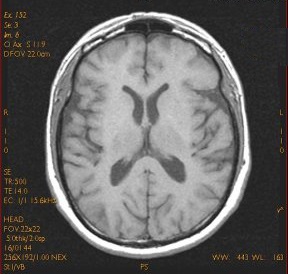

T1 is the time constant for longitudinal relaxation and thermal or spin lattice relaxation. Scan protocols that allow the T1 effects to predominate over the other relaxation effects produce T1-weighted images. In T1-weighted images, tissues with short T1 are bright and tissues with long T1 are dark. In the brain, white matter is brighter than gray matter, and CSF is dark.

T2 is the time constant that measures the transverse magnetization decay and spin-spin effects. Scan protocols that allow the T2 effects to predominate over the other contrast effects produce T2-weighted images. In T2-weighted images, tissues with short T2 are dark and tissues with long T2 are bright. In the brain, CSF produces the brightest signal on moderate to late TE images; pathology that alters and delays T2 also appear bright.

PD-weighted images have contrast that is primarily due to the density of protons in the structures. PD-weighted images result when you select scan timing parameters that minimize the T1 (long TR) and the T2 (short TE) contrast effects. With PD-weighted images, tissues with a greater number of protons are bright and tissues with fewer protons are dark. In the brain, gray matter is brighter than white matter, due to the amount of protons it contains.